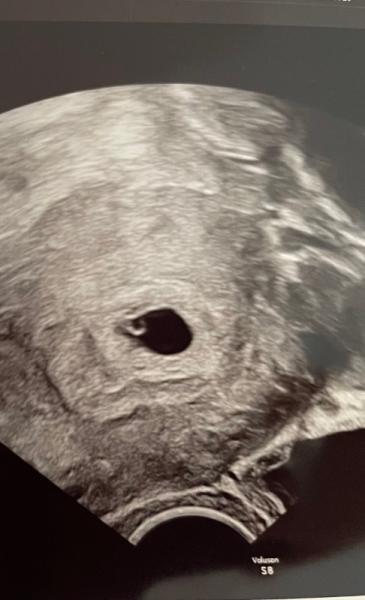

War heute beim Frauenarzt zur Kontrolle bin 5+4 aber man sieht noch nicht so direkt das Herzchen

Hat das jemand von euch auch? Vielleicht ist es ja wirklich noch zu früh . Dottersack und Fruchthöhle ist auch alles da. Musst freitag nochmal hin. Drückt mir die Daumen ihr lieben

Hallo Jen, Witzig, ich bin heute auch 5+4. Gestern hatte ich bei 5+3 US und man sieht eine Fruchthöhle mit Dottersack. Für den Herzschlag ist es noch viel zu früh. Ich hab meinen nächsten Termin am 25.10. - dann wird alles gut sein. Warte, ich lade Dir mein US Bild hoch. Dann kannst Du Vergleichen. Liebe Grüße

Bei 5+4 muss man das auch noch nicht sehen, Dottersack ist doch schon mal prima. Die die eine Herzaktivität bei 5+4 hatten, haben Glück gehabt es sehen zu dürfen.